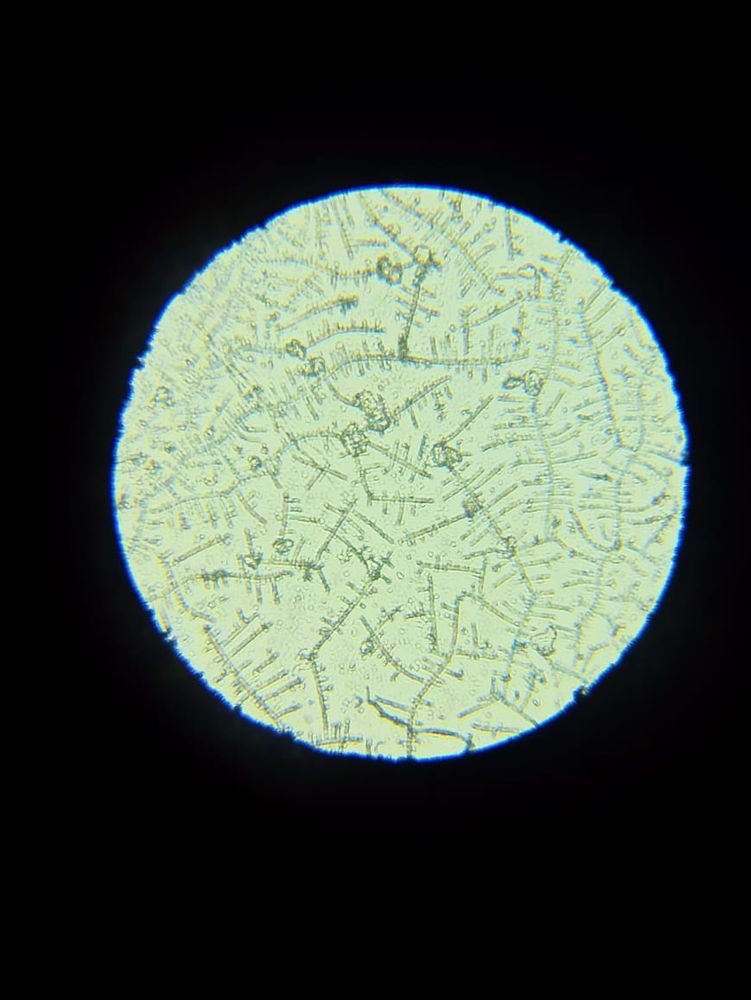

Я читала, что тесты на о показывают б. Возможно ли что и микроскоп на о, показал б.

Я уже ловила о в этом цикле, а по бт поймала из, ну как я думала, как тут вдруг. Вторая о или это первый признак б. Давайте попробуем разобраться. Подобного я р